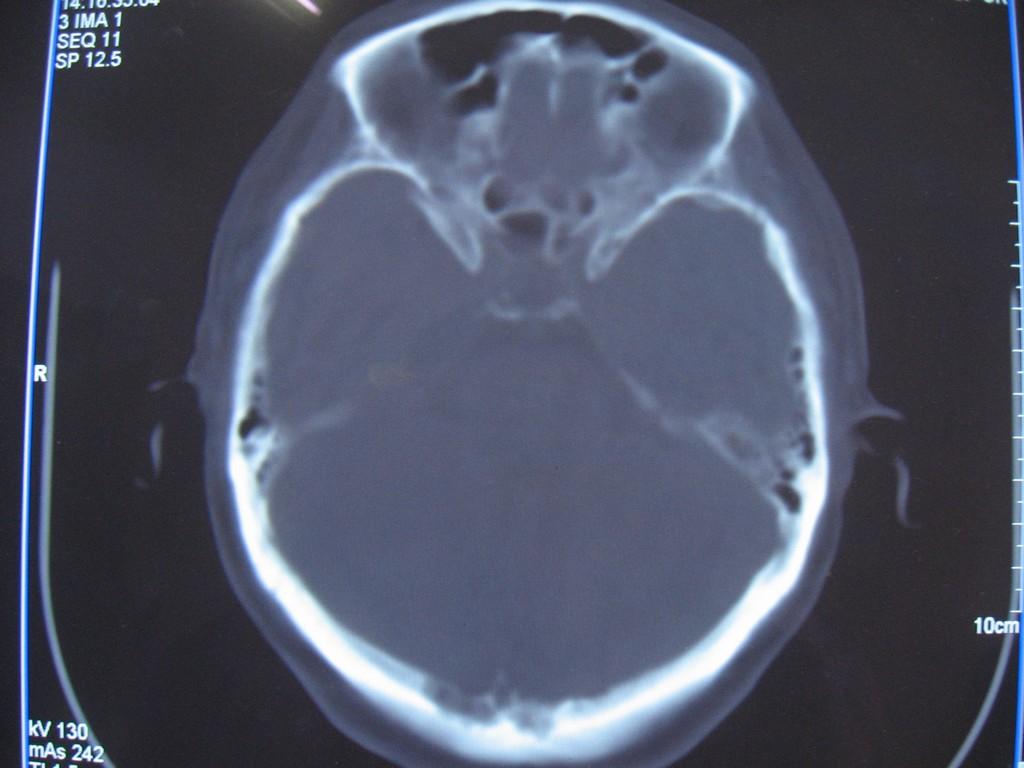

标题: CT22032B:枕骨破坏(从新调整窗宽窗位) [打印本页]

标题: CT22032B:枕骨破坏(从新调整窗宽窗位)

女性病人,53岁,偶尔感枕部针刺样疼痛,ct扫描如下。

蛛网膜颗粒压迹。鉴别:骨巨,嗜酸性肉芽肿,骨髓瘤。

蛛网膜颗粒压迹。

骨巨,嗜酸性肉芽肿,骨髓瘤,动脉瘤样骨囊肿可能

支持蛛网膜颗粒压迹。

支持蛛网膜颗粒压迹,鉴别:骨巨,嗜酸性肉芽肿,骨髓瘤、转移瘤

支持蛛网膜颗粒压迹,嗜酸性肉芽肿发生于30岁以下,基本排除,骨髓瘤、转移瘤多伴有软组织肿块,范围较广。

枕骨蛛网膜颗粒压迹。